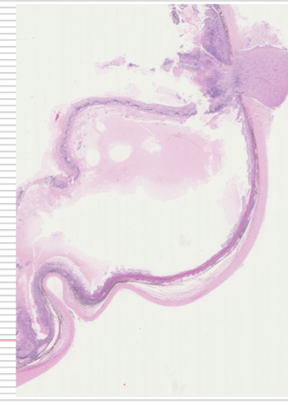

describe abnormalities

A

iris

* deformed

* dyscoria- abnormal pupil shape

* color change

lens

* opaque

* blood vessels

* pigmented

Corneal opacity?